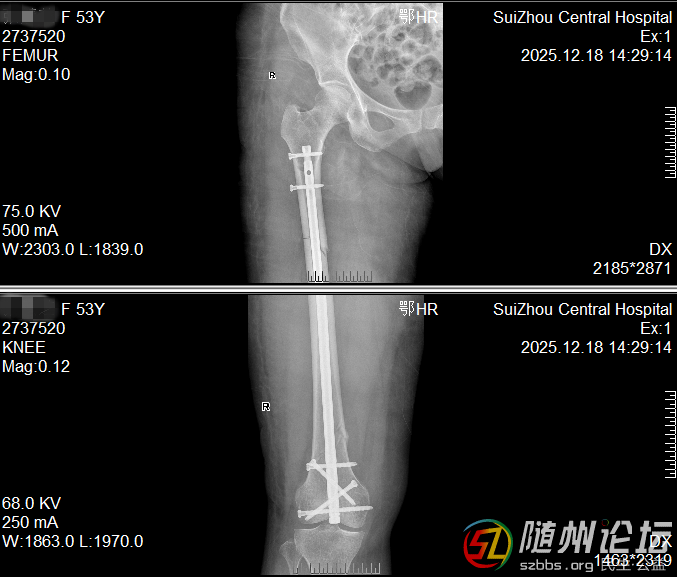

大腿多段骨折,一個小口完成修復(fù)

一位53女士大腿多處骨折,甚至影響到膝蓋。我們僅在膝蓋上方開一個約4厘米的小口,放入一根髓內(nèi)釘將骨折處全部連接固定。這樣既保護了腿部血流和肌肉,也為后期膝蓋活動打下了好基礎(chǔ)。